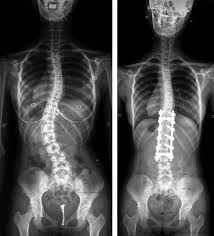

Escoliose

Deformidade da coluna que pode ocorrer por tendências genéticas, síndromes, doenças neurológicas ou desgaste intenso da coluna. Quando diagnosticada precocemente, deve ser acompanhada pois em alguns casos o uso de colete pode ser prescrito. Em casos onde há progressão da deformidade, compressão de nervos, dor intratável, pode-se instituir cirurgias corretivas para a deformidade.